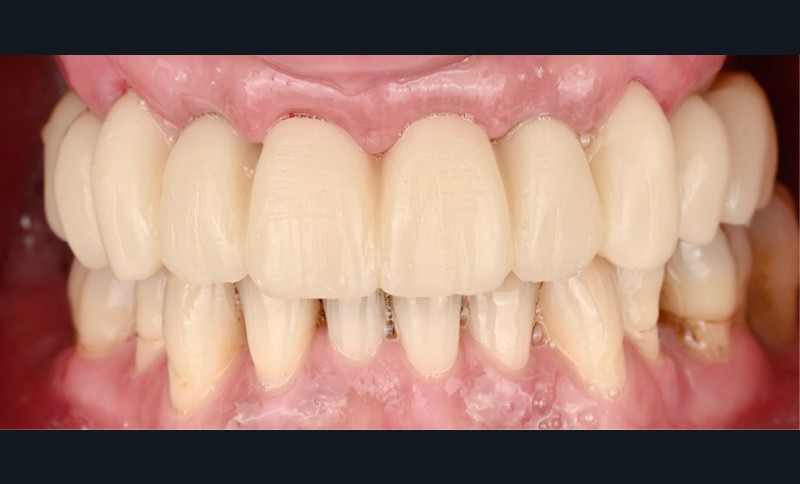

Elle est réalisée en zircone monolithique usinée puis stratifiée manuellement (fig. 9). Dans cette approche hybride numérique-analogique, la CFAO assure la précision de la structure, tandis que la stratification manuelle apporte la personnalisation esthétique et la vitalité du rendu [4]. Le résultat illustre la convergence entre précision technologique et sensibilité clinique (fig. 10).